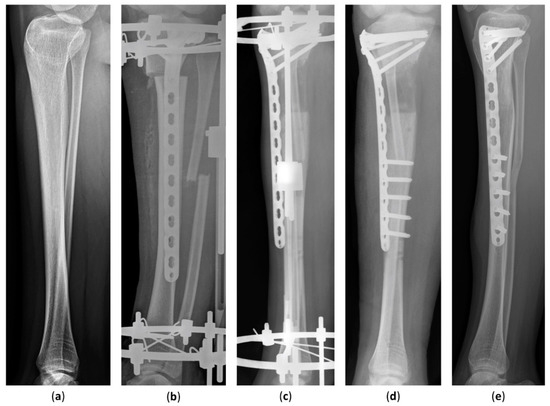

The scanogram was taken in a standing position with both knees fully extended and patellae facing forward. The tibia radiographs were obtained at each clinic visit. The radiographic parameters included leg-length discrepancy, tibial length, length gained, mechanical lateral distal femoral angle (mLDFA), medial proximal tibial angle (MPTA), and mechanical axis deviation (MAD) (Figure 1). The tibial length was measured from the tibial spine to the center of the tibial plafond. The length gained was defined as the increase in length of the operated limb. The mLDFA was defined as the lateral angle between the joint surface of the femoral condyle and the femoral mechanical axis, and the MPTA was defined as the medial angle between the articular axis of the proximal tibia and the tibial anatomical axis [18]. The distance from the center of the knee to the mechanical axis of the lower leg was labeled as the MAD [18]. The MAD was denoted as valgus or varus malalignment when the mechanical axis showed a lateral or medial deviation [18].

Figure 1. Radiological measurements. The superolateral angle between the mechanical axis of the femur and the joint surface of the femoral condyle was defined as the mechanical lateral distal femoral angle (mLDFA). The inferomedial angle between the anatomical axis of the tibia and the articular axis of the proximal tibia was labeled as the medial proximal tibial angle (MPTA). The mechanical axis deviation (MAD) was designated as the distance from the center of the knee to the mechanical axis of the lower leg. Mechanical axis = AB.